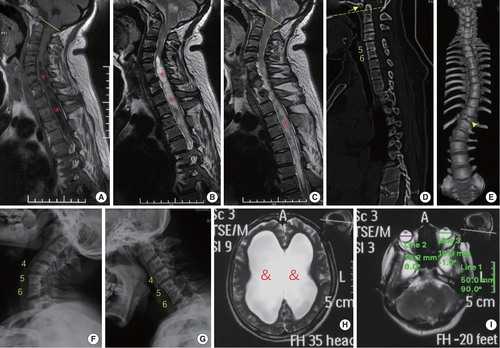

phenotypes of the patient with a premature stop codon of BEST1 gene (p.S79Ffs*153). (A–C) Sagittal magnetic resonance imaging (MRI) revealed Chiari malformation (cerebellar tonsil exceeding the foramen magnum, yellow line) and extensive syringomyelia (red stars) at cervical and thoracic segments. (D–G) Computed tomography and x-ray showed assimilation of atlas (arrow), basilar invagination (odontoid process above the chamberlian line, yellow dotted line), Klippel-Feil malformation (fusion of C5 and C6 vertebrae), butterfly vertebra at T12 (arrow head) and scoliosis. (H, I) MRI of the head indicated hydrocephalus (&) and microphthalmia (diameter of eyeball is smaller than 20 mm).